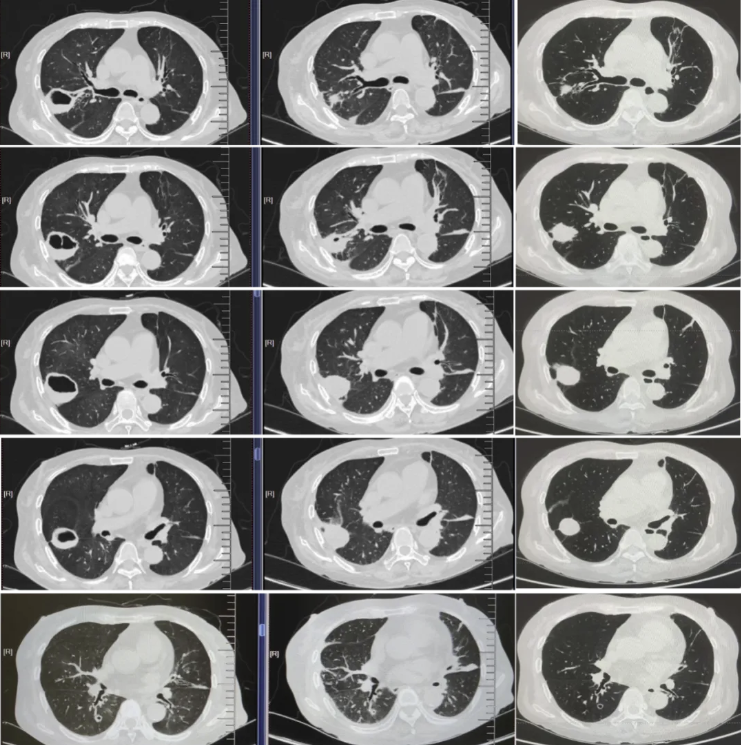

后续为进一步明确肺部病灶性质及有无鼻面部及颅内侵犯,完善胸部增强MRI、头颅MRI及CT引导下肺穿刺检查。

-胸部增强MRI(2025-9-2):1.右肺上叶后段病变(右肺上叶后段见一类圆形异常信号影,大小约3.3x2.7cm,T2WI及抑脂序列呈高低混杂信号,DWI上见弧形高信号影,增强扫描呈环形强化)。 2.双肺散在炎症,部分肺不张。 3.双侧胸腔少量积液。

图5. 胸部增强MRI (2025-9-2)

-头颅MRI平扫(2025-9-3):1、脑白质高信号,Fazekas 1级;老年脑改变。 2、双侧筛窦炎。